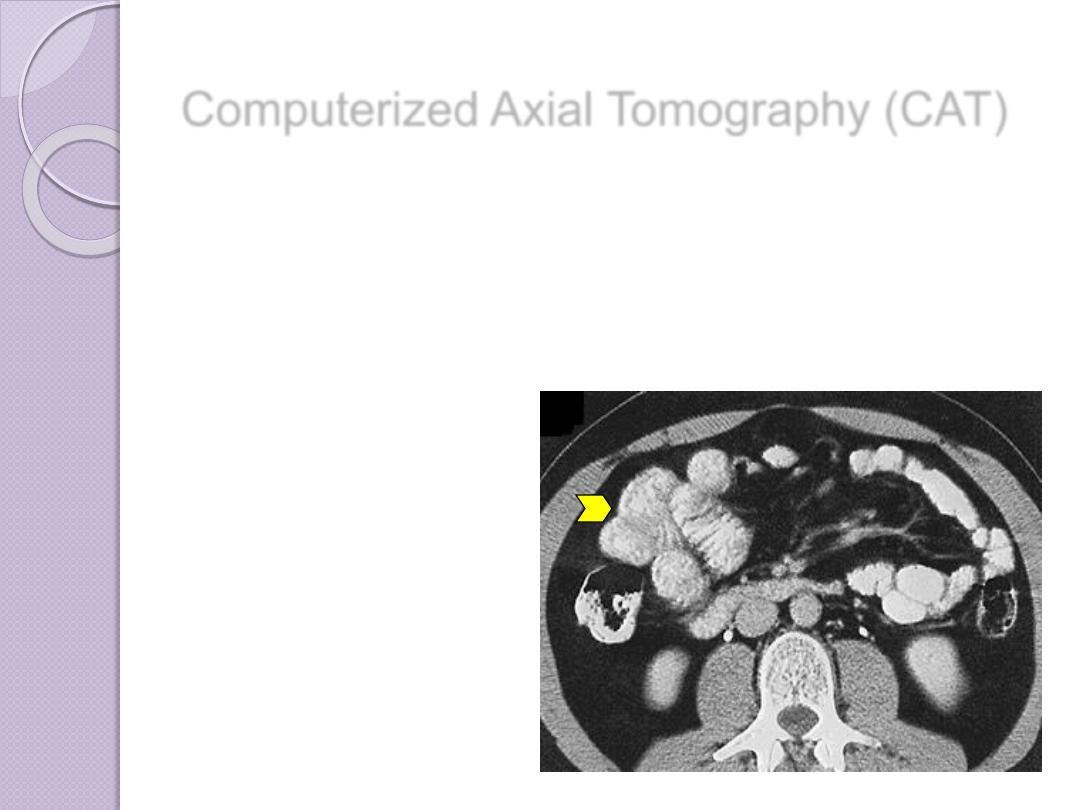

Computerized Axial Tomography (CAT)

Important diagnostic

information about tissues

in the scanned regions of

interest is thereby made

Contrast enhancement

may be used

Contrast enhancement of

the bowel after oral

administration of barium